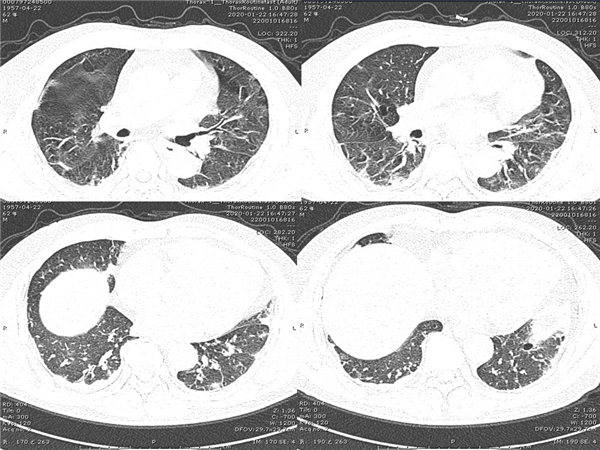

【病例分享】新型冠狀病毒感染肺部CT影像4例(常德市第一人民醫(yī)院)

幻燈片7.jpg